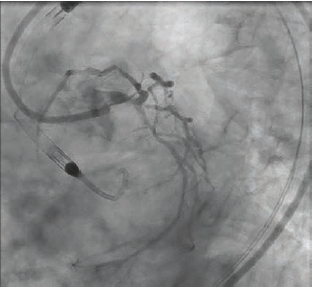

Yes, there are various axes of considerations. One that is commonly discussed is whether mechanical support is needed. Here we are really lacking in data and it comes down to judgment on the part of the operator. We have to take into account the ejection fraction, as well as hemodynamics and filling pressures regardless of the ejection fraction. Is there severe left main bifurcation disease that requires rotational atherectomy or is this just a simple ostial left main lesion? All of that goes into the hemodynamic concerns. For bifurcation technique, is it reasonable to use a provisional technique or do you need a two-stent technique? If so, what should that be? The best data we have support DK crush as the typical routine approach to the bifurcation. And then, of course, intracoronary imaging. We don’t have a lot of data specifically for the left main, but we know from many randomized trials with complex coronary disease, broadly defined, that people do better after PCI using intracoronary imaging. The data are overwhelming at this point. Technique is important, however, with optical coherence tomography (OCT) or intravascular ultrasound (IVUS). What exactly did you do with the data? My own practice has evolved significantly. We took part in a project called LightLab where a clinical field engineer was present in the cath lab with us. During angiography, not just for a left main, but for any PCI we were doing, we would estimate, based on the angiogram, the reference vessel diameter distally and proximally, the lesion morphology, and the lesion length, among other variables. Then we would do OCT and repeat the same evaluation. It was humbling to realize how difficult it is to be accurate with an angiogram alone. Today, that pre-PCI OCT or IVUS is hugely important. You can plan the entire procedure. You know how big the vessel is supposed to be, you know what the 1-to-1 balloon is and can see if the balloon is expanding appropriately. The historical view of imaging is that it is something done at the end of the procedure to check your work. The modern view is very different. You do intravascular imaging up front, plan your procedure and execute it, and then, on the back end, use it to make sure you have obtained the expected result.